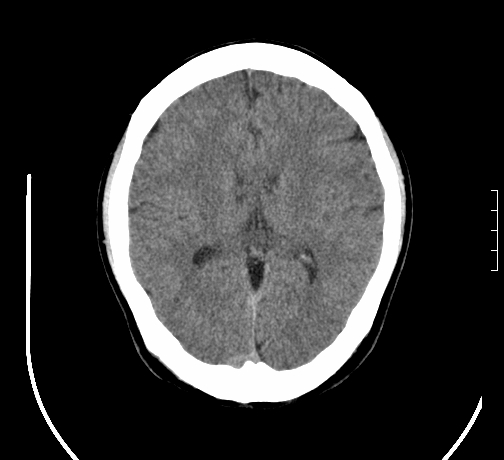

女,28岁,幼时有癫痫,常有发作,服药后可几月不发作,走路不稳3-4月,加重一月。

小脑发育畸形?

小脑萎缩。

考虑小脑发育不良,建议mri检查。

患者出现走路不稳是近几个月的事,而癫痫则有幼时就有,常发,则会常服药,癫痫药可引起小脑综合症,小脑萎缩,而小脑发育不良的主要症状不是癫痫

考虑癫痫,长期间断发服抗癫药,导致小脑综合症,小脑萎缩

考虑小脑发育不良伴小脑萎缩,建议mri检查。

小脑萎缩,原因待查,建议mri检查。